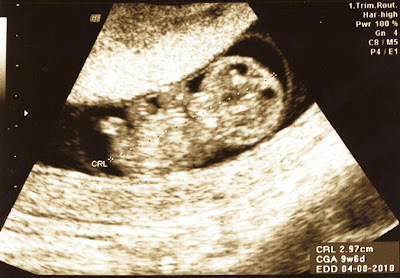

Just a quick note: The baby was practically doing jumping jacks and somersaults in this ultrasound and it was my first real "Holy crap - it's alive and inside of me..." moment. Pretty spectacular. And strange.

I would like to share some of the interpretations of my little baby's ultrasound with all of you. So far, this is what we've got:

gastropod

three-legged cyclops (this, from my husband...)

alien baby

"Congratulations! you're having a turtle"

"Why are you having a turtle?"

little nugget, or simply "nugget"

three-armed freak & weirdo

Then again, with all of the turtle interpretations - maybe we should start calling the baby "Little Dude."